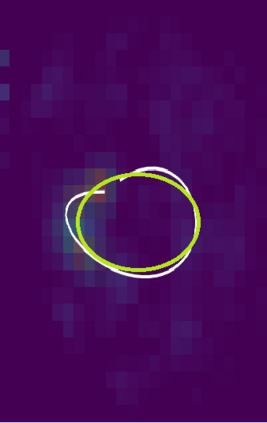

Various imaging modalities allow for time-dependent image reconstructions from measurements where its acquisition also has a time-dependent nature. Magnetic particle imaging (MPI) falls into this class of imaging modalities and it thus also provides a dynamic inverse problem. Without proper consideration of the dynamic behavior, motion artifacts in the reconstruction become an issue. More sophisticated methods need to be developed and applied to the reconstruction of the time-dependent sequences of images. In this context, we investigate the incorporation of motion priors in terms of certain flow-parameter-dependent PDEs in the reconstruction process of time-dependent 3D images in magnetic particle imaging. The present work comprises the method development for a general 3D+time setting for time-dependent linear forward operators, analytical investigation of necessary properties in the MPI forward operator, modeling aspects in dynamic MPI, and extensive numerical experiments on 3D+time imaging including simulated data as well as measurements from a rotation phantom and in-vivo data from a mouse.